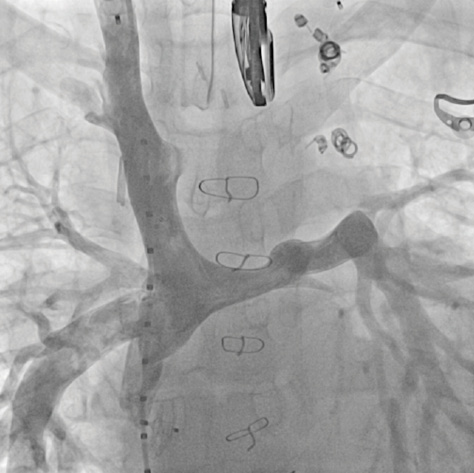

Coronary angiography showed multiple fistulas between the inferior vena cava and the pulmonary veins/left atrium (Figure 2). Three of those veins were embolized by implanting Amplatzer plugs (10-mm Plug II, 12-mm Plug II, 6-mm Plug IV) (Figure 3). After a 3-hour procedure, it was decided to stop and to postpone further treatment of the other fistulas. Her systemic oxygen saturation had increased to 88%. However, the patient still experienced palpitations, facial flush, and sporadic events of systemic arterial hypertension. Furthermore, events of hemoptysis and acute dyspnea occurred.

Figure 2. Angiography of the inferior vena cava in the anteroposterior view showing multiple venous/left atrial collaterals.